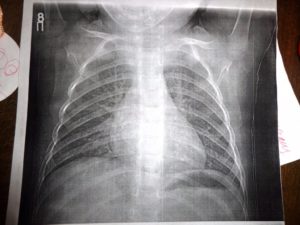

Клинически повторное заболевание, как правило, проявляется значительно сильнее, чем первичный случай. Однако на начальных этапах его трудно распознать, поскольку пациент может считать, что вновь появившиеся симптомы являются следствием ранее перенесенной болезни. Рентгенологическое обследование легких играет ключевую роль в определении характера протекания заболевания.

- Рентгенологическое исследование демонстрирует увеличение пораженной области или изменение характера заболевания на очаговое, что подразумевает наличие множественных поражений.

Установить более точный диагноз с определением степени поражения легкого (также, как распознать бронхит у ребенка и любое другое бронхолегочное заболевание) можно с помощью рентгенографии.

В медицинских источниках можно встретить различные определения повторной пневмонии. В педиатрической практике это заболевание характеризуется как два или более случая в течение одного календарного года, либо более трех эпизодов за неограниченный период времени. При этом рецидив подтверждается рентгенографическими данными, которые показывают освобождение легочной ткани при наличии инфильтрации.